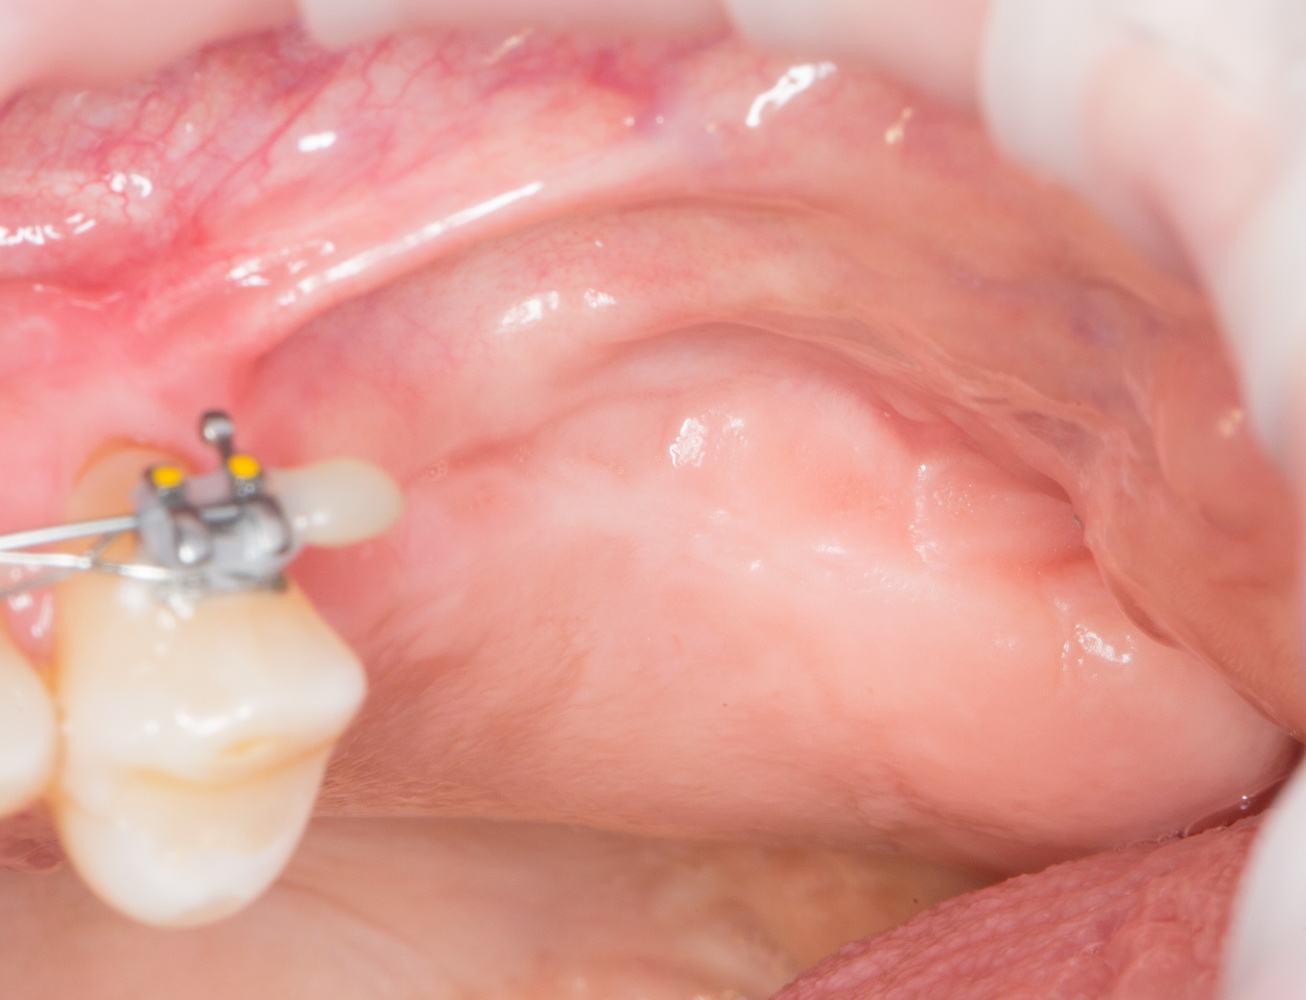

Картинка через четыре месяца:

11  12

Круто, правда? Теперь у нас есть возможность сказать «бе-е-е» тем, кто говорил, что это невозможно и спокойно поставить импланты.